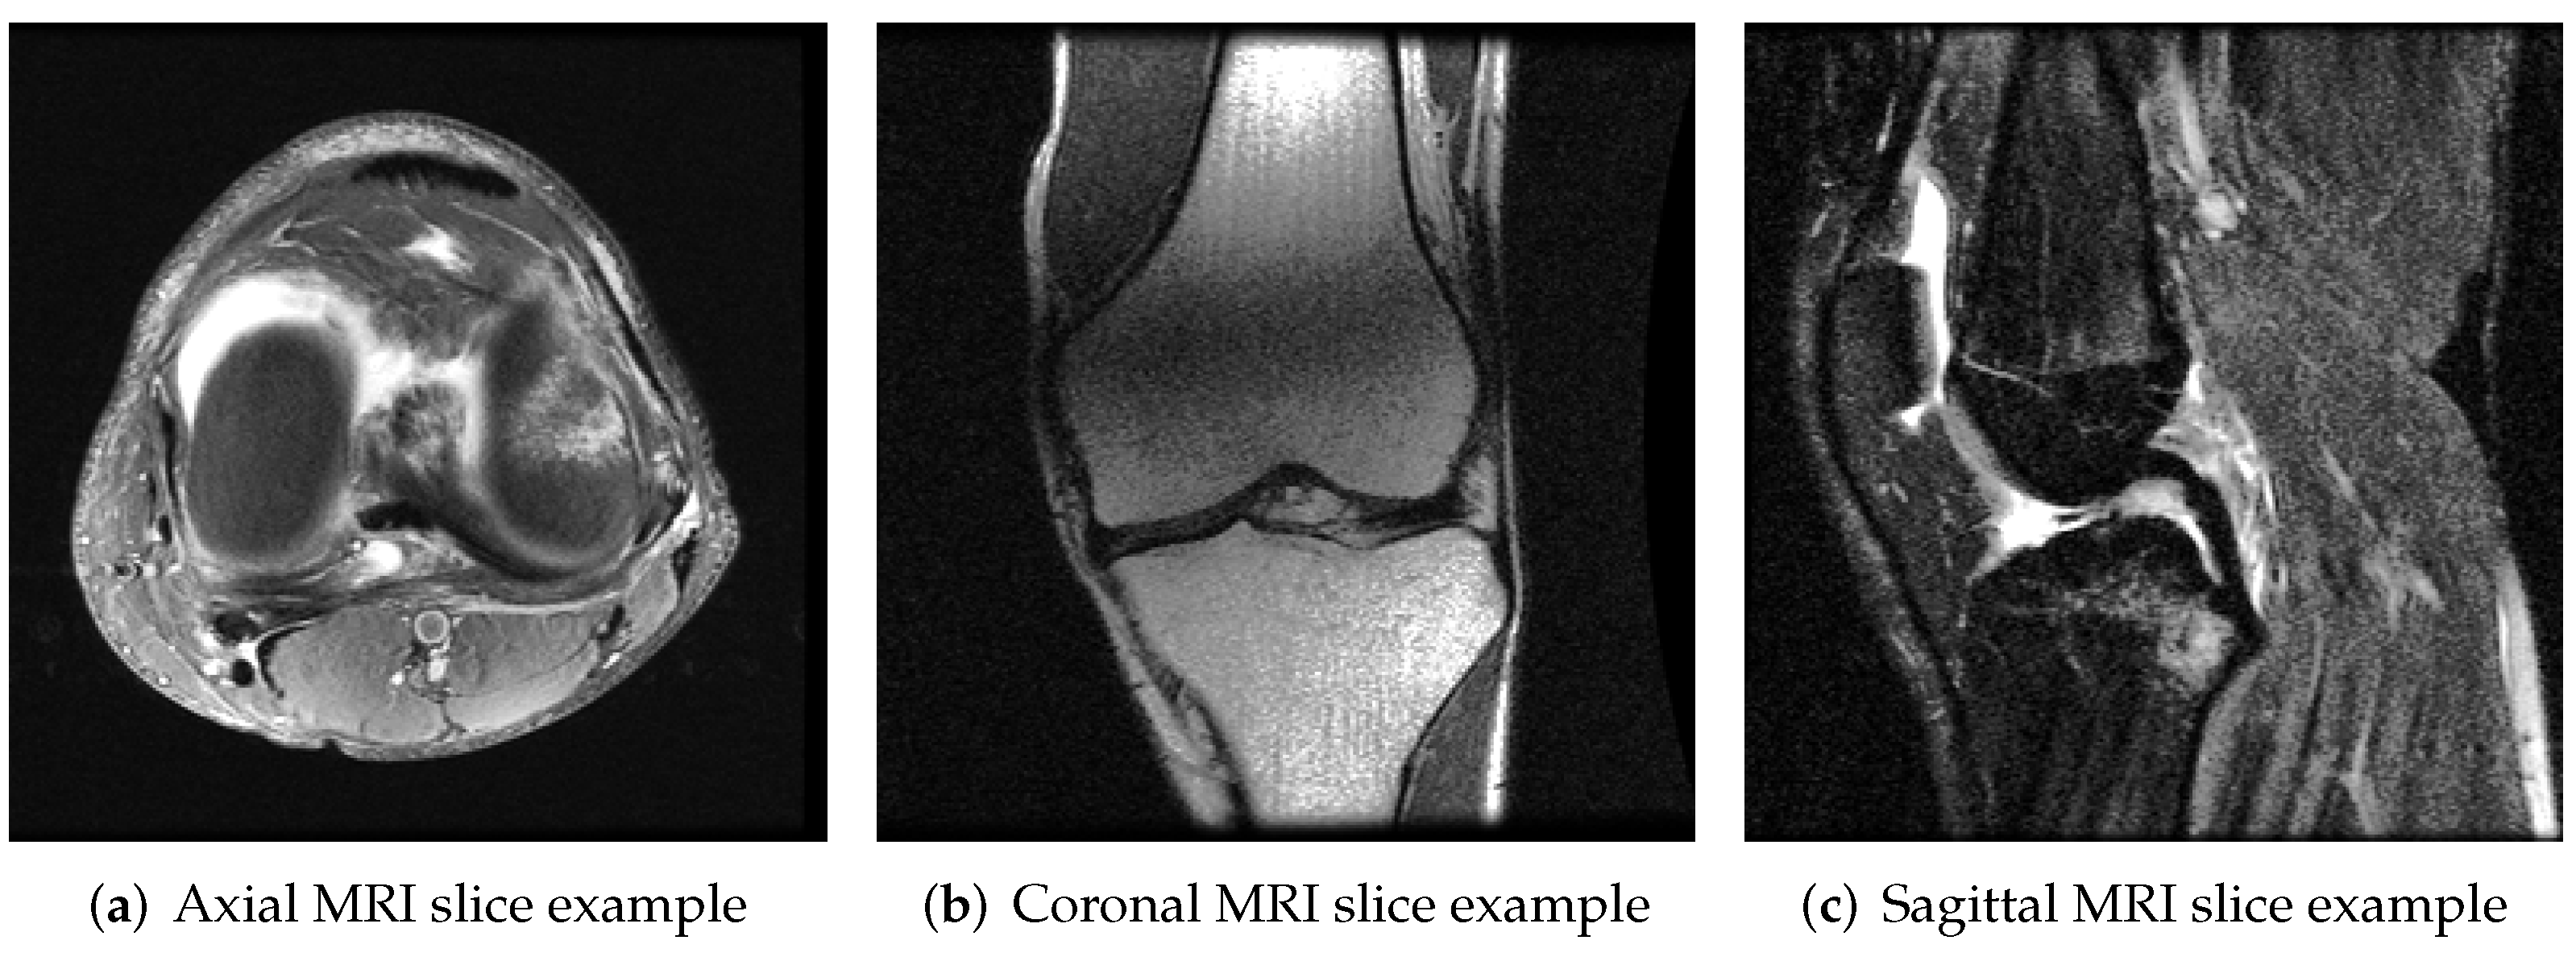

The MRNet dataset consists of 1370 knee MRI exams performed at Stanford University Medical Center. The dataset contains 1104 (80.6%) abnormal exams, with 319 (23.3%) ACL tears and 508 (37.1%) meniscal tears; labels were obtained through manual extraction from clinical reports [11]. Examples of middle slice knee MRI images are shown in Figure 2.

Figure 2. Input image examples of MRNet. Three images represent (a) axial, (b) coronal and (c) sagittal knee MRI planes.